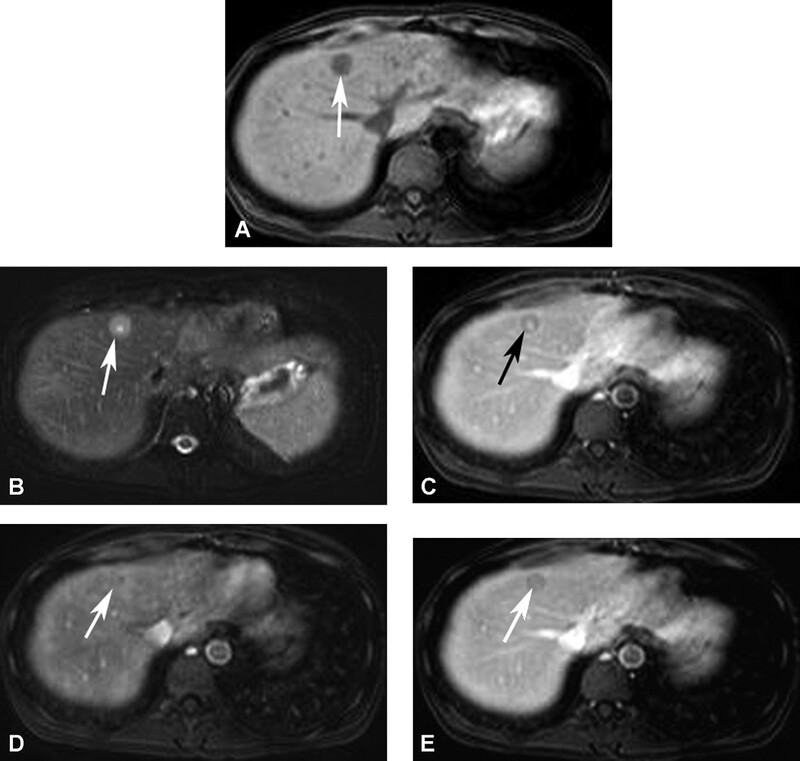

Di căn đến gan từ các u nguyên phát như u tế bào tiểu đảo/thần kinh nội tiết, carcinoid, carcinoma tế bào thận, melanoma và carcinoma tuyến giáp thuộc về nhóm di căn gan giàu mạch máu. Trên siêu âm di căn là các tổn thương giảm âm. Vùng trung tâm hoại tử có thể giảm âm hoặc echo trống. Hầu hết di căn giảm đậm độ trên CT không cản quang. Di căn của u thần kinh-nội tiết có thể tăng đậm độ trên CT không cản quang. Hầu hết các di căn giàu mạch máu bắt quang sớm mô u sống ở thì động mạch và giảm đậm độ với nhu mô gan ở thì tĩnh mạch cửa (Hình 14-18). T2W có tín hiệu thay đổi, thường tăng tín hiệu trung bình và giảm tín hiệu trên T1W, Melanoma là một ngoại lệ, ở đó tích tụ melanin, có tính chất rút ngắn thời gian T1, có thể dẫn đến tín hiệu cao trên T1W (Hình 19). Bắt Gd đặc trưng cho thấy tổn thương rõ rệt nhất ở thì động mạch với viền bắt thuốc ngoại vi điển hình (Hình 20C).

Hình 17. U tế bào tiểu đảo di căn gan. Nhiều ổ di căn ấyở gan là các ổ giảm tín hiệu trên T1W (A) và tăng tín hiệu trên T2W (B). Ghi nhận khối lớn nhất cấp máu quá mức và gây hoại tử trung tâm có tín hiệu thấp trên T1W (A, mũi tên) và tín hiệu cao trên T2W (B, mũi tên). Tất cả các tổn thương bắt thuốc viền ngoại vi mạnh ở thì động mạch (C, tổn thương lớn nhất được đánh mũi tên), thải thuốc nhanh ở thì tĩnh mạch cửa (D, tổn thương lớn nhất được đánh mũi tên). Vùng trung tâm trong tổn thương lớn nhất (mũi tên ở E) nghèo mạch máu và không bắt thuốc ở thì động mạch, nhưng thường có thể tụ tập thuốc tương phản ở thì mô kẽ trễ.